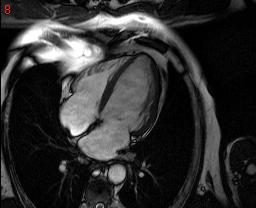

cardiac mri is some thing which can save many lives but the software available to analyse them are too costly...

the pictures show a few cardiac MRI data.. is there any way we can crop out hust the heart ,

itried a few thresholding scheles but, they dont seem to work very well